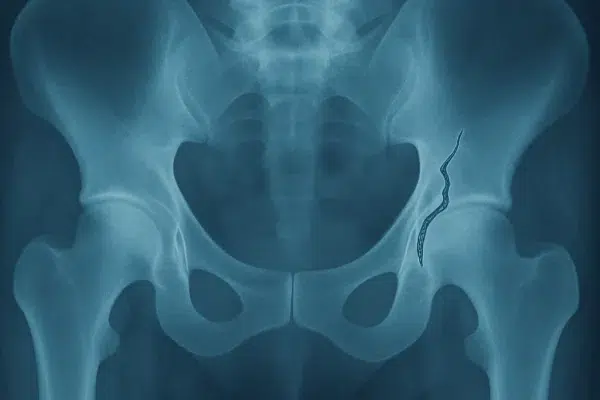

Ejercicios de la fase 2 en la rehabilitación de prótesis de cadera 🦵✨

La fase 2 de la rehabilitación tras una prótesis de cadera es el momento en el que muchos pacientes empiezan a “sentirse de verdad en recuperación”: el dolor agudo suele disminuir y se puede trabajar con más intensidad la fuerza, el equilibrio y la marcha….